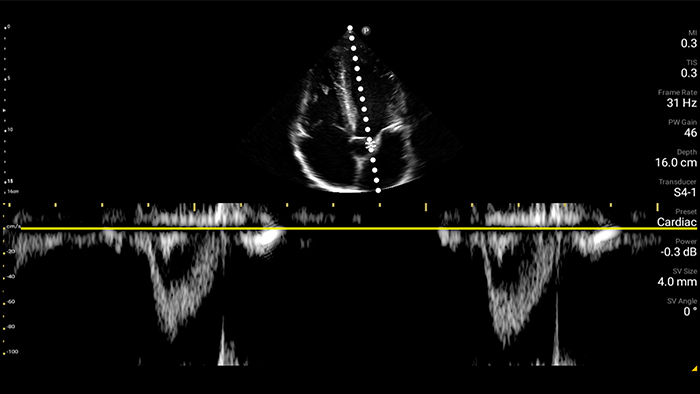

Assessment of left ventricular function

From revealing the subtle details of an image to uncovering enriched tissue definition from multiple angles, Lumify can help you make real-time decisions with more confidence from assessment through recovery.